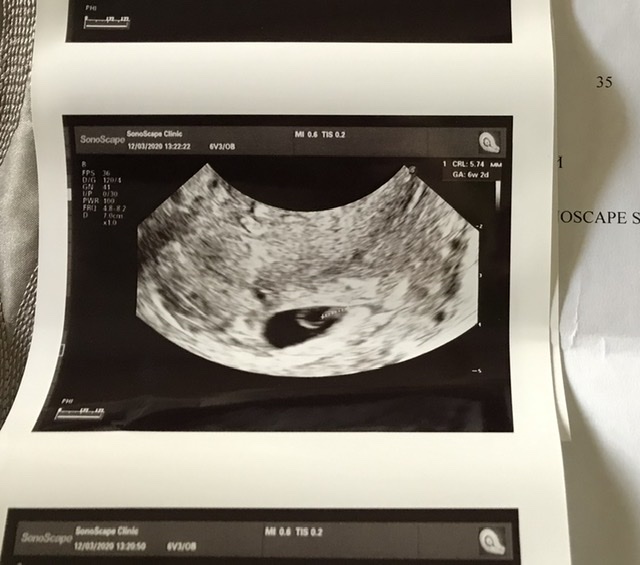

Девушки, добрый день) Случайно натолкнулась на этот метод определения пола и очень заинтересовал. Помогите пожалуйста понять где у меня этот самый хорион))) Не могу определить и понять кого же я ношу сейчас)

У меня оказалась неразвивающаяся беременность, что сожалению(( Я так и не узнала кто

Судя по этому фото и методу у вас мальчик, но у меня был эмбриончик конкретно справа, жду девочку... В общем, не совпало)